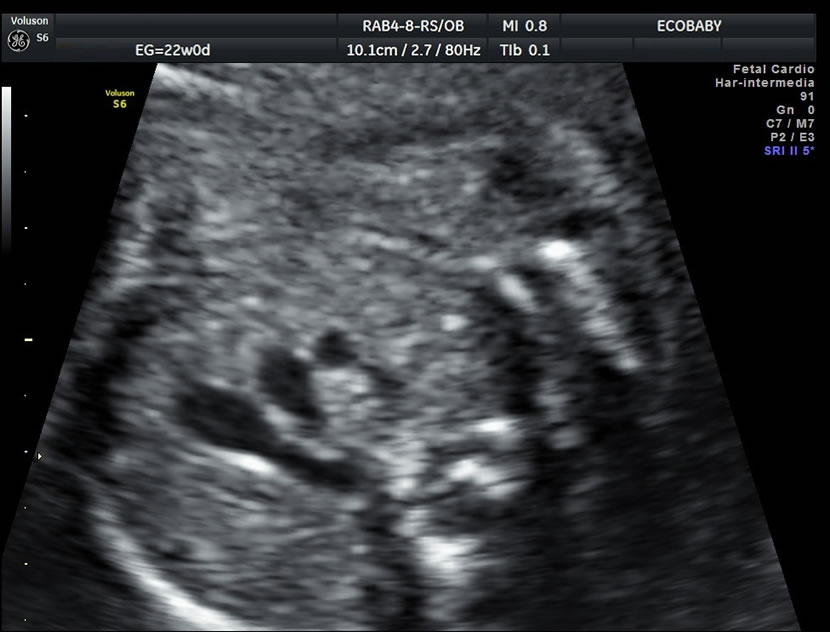

Cerebro, cuello, cara, tórax, corazón (diferentes cortes que muestran las cavidades y la correcta entrada y salida de arterias y venas), abdomen (normalidad de la pared, estómago, intestino, riñones, vejiga), miembros inferiores y superiores y columna vertebral.